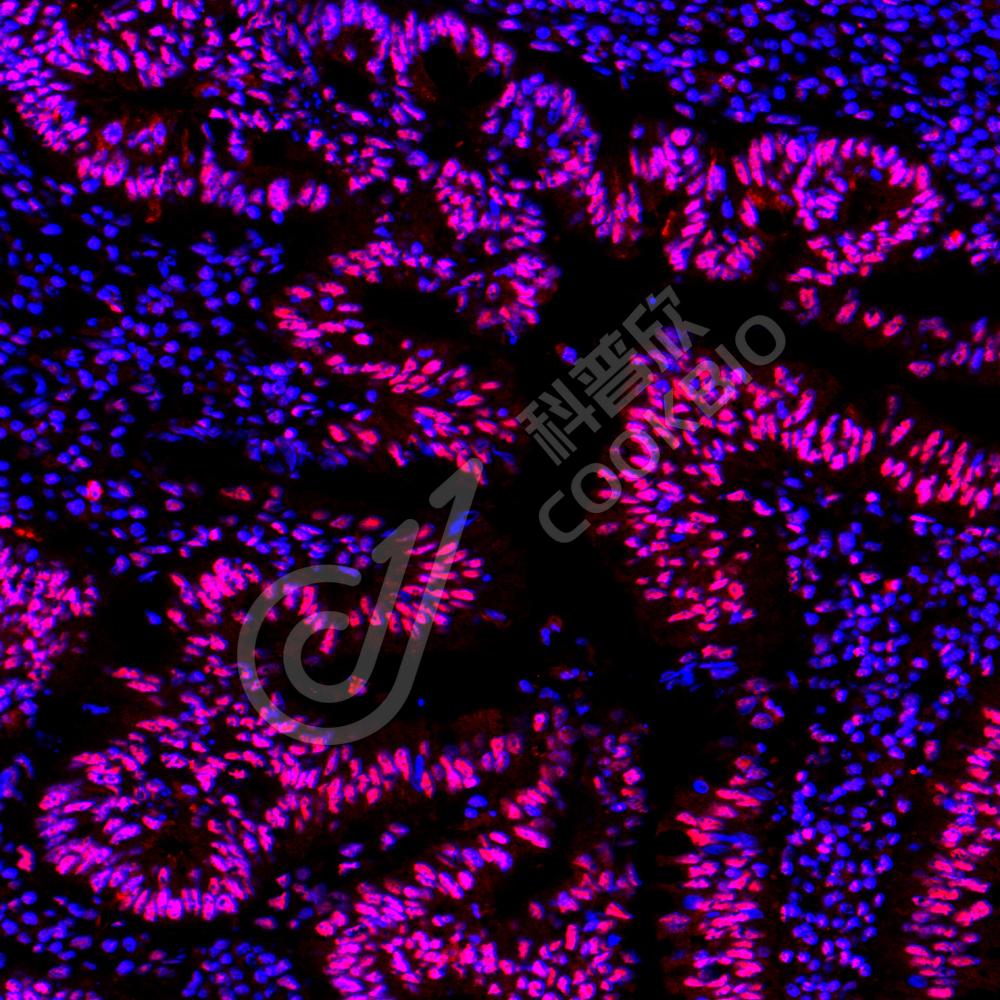

ICC/IF 免疫细胞化学/免疫荧光

物种:人

稀释比:1:500-1:1000

阳性样品:—